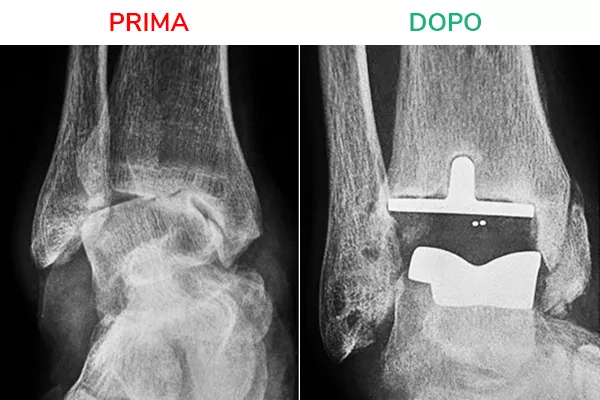

Radiografia in movimento

La radiografia in movimento mostra lo spazio articolare ripristinato e la distanza tra tibia e astragalo. Il movimento risulta fluido e scorrevole, simile a quello fisiologico. Il risultato che si deve ottenere al termine dell’intervento di Protesi di Caviglia è la normale mobilità della caviglia in flesso-estensione.